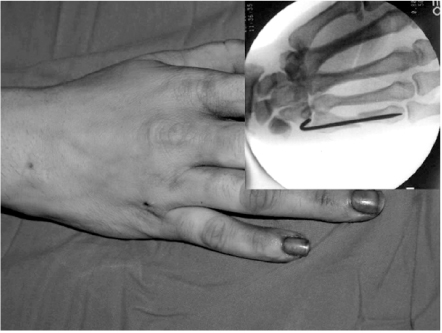

The surgery was performed under general or regional anesthesia with image intensification, preferably with a tourniquet on the upper arm. Under the fluoroscopy, closed reduction of the metacarpal fracture was achieved by manipulation, and 1.6 mm K-wire was inserted from metacarpal head with MP joint flexion for easy access to the medullary canal (Fig. 1). When the wire tip passed fracture site and reach to metacarpal base, wrist was bent maximum and further penetration was performed to proximal area (Fig. 2). The distal end of K-wire was pulled up until its tip end lay within the metacarpal head (Fig. 3). Penetrated proximal part of wire was bent over, cut and buried under the skin (Fig. 4). During this procedure, any rotation of fracture was carefully checked with passive flexion and extension motion of the finger. Ulnar gutter splint was applied for rotational stability and pain relief. It was changed to extension block splint and encouraged motion exercise from postoperatively 1 week. After fracture healing, the wire was removed with local anesthesia in the outpatient department in all cases. We make small skin incision at proximal bended wire and pull out that with local anesthesia.

Fig. 1

1.6 mm K-wire is inserted from metacarpal head with metacarpophalangeal joint flexion for easy access to the medullary canal.

Fig. 1 1.6 mm K-wire is inserted from metacarpal head with metacarpophalangeal joint flexion for easy access to the medullary canal.